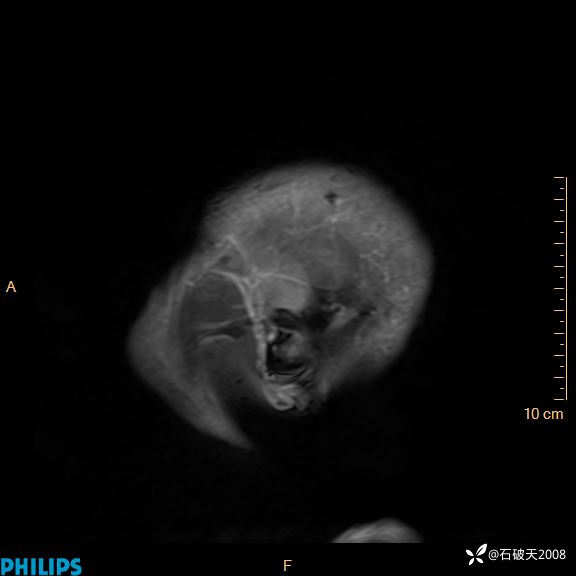

2024.2.21MR

增强矢状位